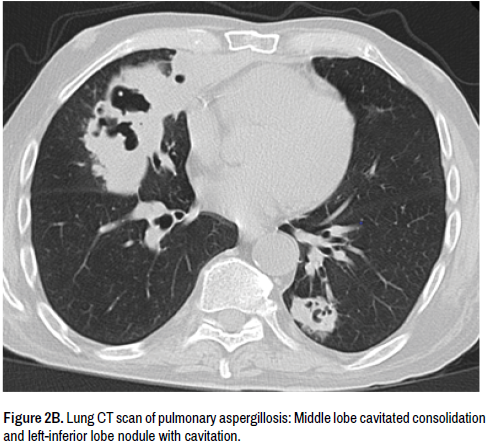

A 76-year-old man was admitted to our Unit after seven days of pyrexia, productive cough and hemoptysis. His medical history was: 15-years COPD and steroid treatment, complete surgical resection and adjuvant radiotherapy of asymptomatic thymoma, decompensated heart disease with persistent atrial fibrillation, and HCV (CHC). Six weeks before the admission he suffered from bronchitis and a chest X-ray showed small nodule in the right superior lobe treated with levofloxacin for 10 days (Figure 1A). Radiographic signs of infiltration in the upper part of the right lung were found at Hospital admission (Figure 1B). A chest CT-revealed a 100 mm diameter cavitary mass complex in the upper lobe of the right lung, surrounded by nodules in both lungs (Figures 2A and 2B). Hemoptysis at admission was mild. Pulmonary tuberculosis was ruled out. Initial management included crystalloids, empiric antibiotics (piperacillin/tazobactam) as suspicion of pneumonia. Despite receiving 72 hours of intravenous antibiotics the fever increased. Blood Aspergillus galactomannan antigen was positive confirming evidence of invasive aspergillosis. Aspergillus spp. and Candida albicans was isolated from his endotracheal aspirate (Figures 3A and 3B). Antifungal triazole isavuconazole and the echinocandin micafungin were started [5]. His fever disappeared after three days. Unfortunately, massive hemoptysis occurred getting worse his cardiorespiratory system and deteriorated kidney function and patient died.

Figure 2B. Lung CT scan of pulmonary aspergillosis: Middle lobe cavitated consolidation and left-inferior lobe nodule with cavitation.